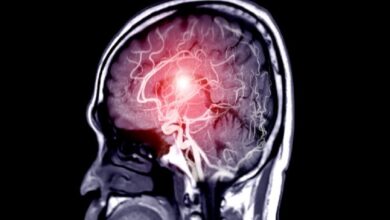

نمایش التهاب مغزی برای اولین بار با استفاده از نوعی جدیدی از ام.آر.آی

دانشمندان برای اولین بار از تصویربرداری رزونانس مغناطیسی یا همان امآرآی(MRI) برای نشان دادن التهاب مغز استفاده کردند که این…